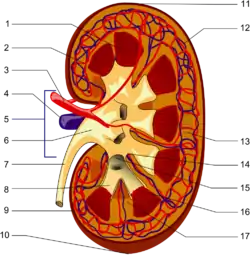

Before reaching the hilus of the kidney, each artery divides into four or five branches. The anterior branches (the upper, middle, lower and apical segmental arteries) lie between the renal vein and ureter, the vein being in front, the ureter behind. The posterior branches, which are fewer in number and include the posterior segmental artery, are usually situated behind the ureter.[7]

Each vessel gives off some small inferior suprarenal branches to the suprarenal gland, the ureter, and the surrounding cellular tissue and muscles.

One or two accessory renal arteries are frequently found, especially on the left side since they usually arise from the aorta, and may come off above (more common) or below the main artery. Instead of entering the kidney at the hilus, they usually pierce the upper or lower part of the organ.